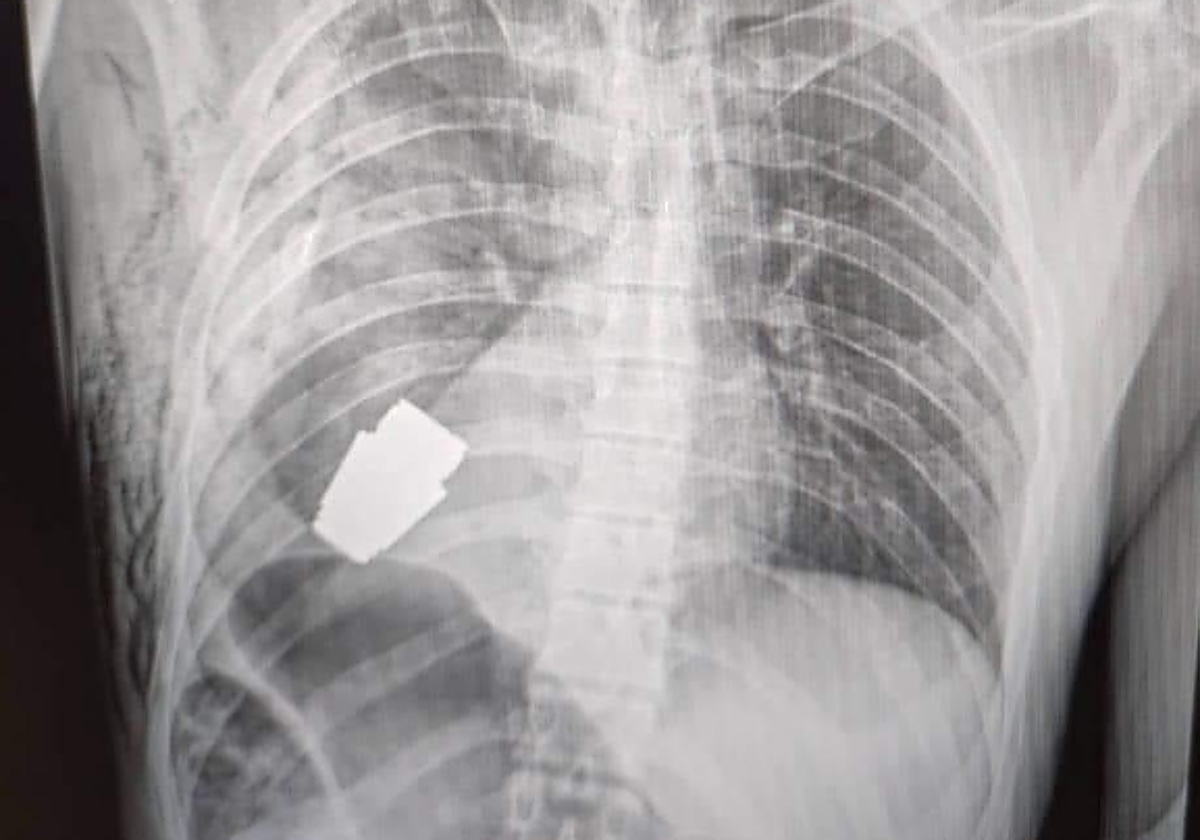

Médicos militares han realizado con éxito una operación a uno de los soldados ucranianos que combate en la guerra contra Rusia para extraerle una granada VOG de la zona torácica que no había sido detonada y permanecía activa.

Así lo ha anunciado la ... ministra de Defensa ucraniana, Hanna Maliar, que ha celebrado que «no todas las heridas en la zona cardíaca son mortales». La operación, según ha informado Maliar, fue realizada por uno de los cirujanos más experimentados de las Fuerzas Armadas de Ucrania, Andrew Willow, sin electrocoagulación, ante el riesgo de que la granada pudiera detonar en cualquier momento.

El artefacto fue retirado en presencia de dos zapadores, militares especializados, que garantizaron la seguridad del personal médico. La intervención terminó con éxito y el militar herido fue trasladado para seguir la rehabilitación y recuperación.

No obstante, sigue siendo un misterio incluso para los expertos el hecho de que el soldado, cuya identidad no ha salido a la luz, pudiera alojar dicho artefacto en el interior de su cuerpo sin que haya detonado.